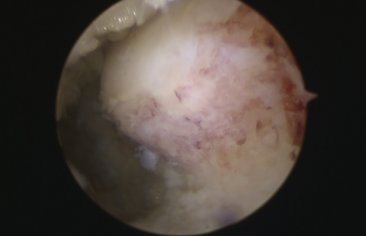

镜下刨削刺激病变的距骨软骨

镜下打入锚钉固定距腓前韧带

术中,探查见关节腔大量增生病变滑膜组织,距骨软骨面多处软骨剥脱变性,明显的外侧副韧带损伤后继发关节炎表现。手术医生在踝关节镜下刨削刺激病变的距骨软骨,打入锚钉固定距腓前韧带,圆满完成手术。